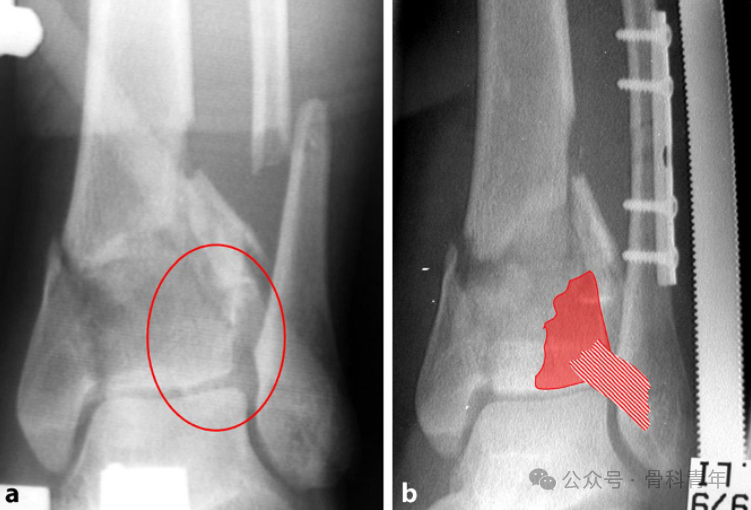

恢复腓骨长度; -

恢复胫骨远端关节面平整; -

胫骨干骺端植骨; -

胫骨内侧钢板固定。

6.2 胫骨关节面复位固定

6.3

植骨

6.4

内侧支持钢板固定